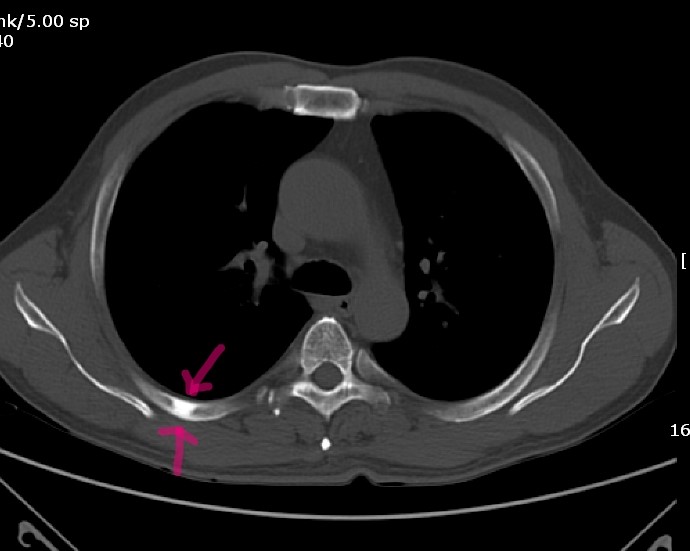

Rib Bone Island . Bone island, also known as enostosis, is a benign bone lesion commonly found on radiographs. They sometimes resemble other types of lesions. • asymptomatic focal areas of bony sclerosis. A bone island, also known as an enostosis, is a focus of compact bone located in cancellous bone (see the images below). Bone islands are lesions which are composed of dense bone within another bone in your body. A bone island is a harmless piece of compact bone inside cancellous bone. It appears as a small, circular, opaque area within. They are round and small (2 to 20 mm) intramedullary. Bone islands, previously known as enostoses, are common benign sclerotic bone lesions that usually represent an incidental finding. Bone islands almost never cause. You might need a biopsy if it causes pain. This is a benign entity that is usually found. Bone island, also called an enostosis, is a benign bone tumor mostly encountered as an incidental and asymptomatic finding.

Rib Bone Island A bone island is a harmless piece of compact bone inside cancellous bone. Bone island, also called an enostosis, is a benign bone tumor mostly encountered as an incidental and asymptomatic finding. You might need a biopsy if it causes pain. Bone islands almost never cause. Bone islands, previously known as enostoses, are common benign sclerotic bone lesions that usually represent an incidental finding. A bone island, also known as an enostosis, is a focus of compact bone located in cancellous bone (see the images below). It appears as a small, circular, opaque area within. They are round and small (2 to 20 mm) intramedullary. • asymptomatic focal areas of bony sclerosis. Bone islands are lesions which are composed of dense bone within another bone in your body. This is a benign entity that is usually found. Bone island, also known as enostosis, is a benign bone lesion commonly found on radiographs. They sometimes resemble other types of lesions. A bone island is a harmless piece of compact bone inside cancellous bone.

An enostosis (pl. enostoses, also known as a "bone island") is a common Rib Bone Island A bone island is a harmless piece of compact bone inside cancellous bone. It appears as a small, circular, opaque area within. Bone islands almost never cause. They sometimes resemble other types of lesions. • asymptomatic focal areas of bony sclerosis. Bone island, also known as enostosis, is a benign bone lesion commonly found on radiographs. Bone islands, previously known. Rib Bone Island.

Bone Island Radiology Key Rib Bone Island Bone islands, previously known as enostoses, are common benign sclerotic bone lesions that usually represent an incidental finding. Bone island, also called an enostosis, is a benign bone tumor mostly encountered as an incidental and asymptomatic finding. Bone island, also known as enostosis, is a benign bone lesion commonly found on radiographs. This is a benign entity that is usually. Rib Bone Island.